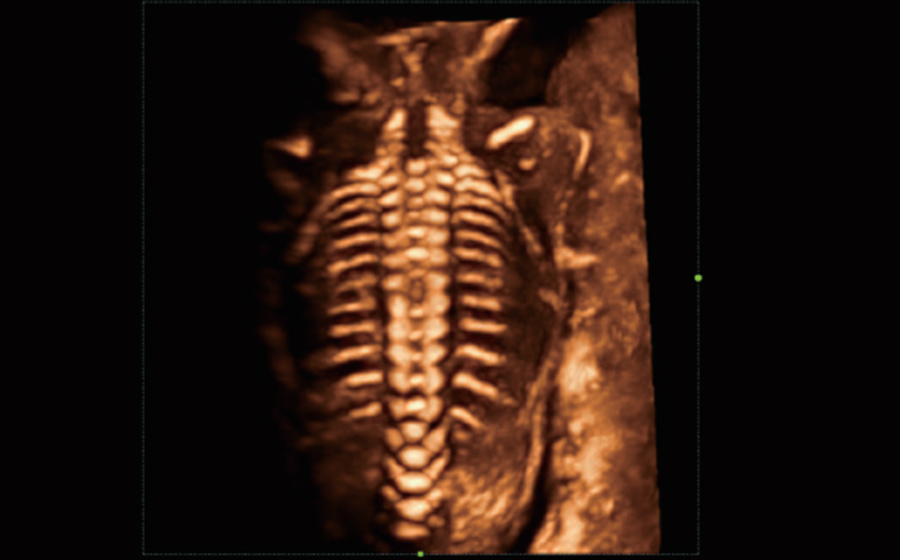

Gambar Klinis